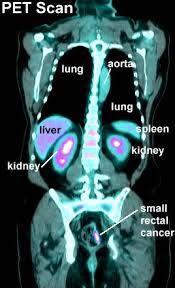

Ct scans overstaged and understaged ct in 23.7% and 48.3% and cn in 28.7% and 53.0% of cases. The endoscopy has an additional benefit of allowing small polyps to be biopsied or removed. The scan is painless and takes about 10 to 30 minutes. None of my ct scans report about the colon tumour. I performed an scope examination of her esophagus and confronted a huge cancer occupying the lower portion of her esophagus. Ct colonography (also known as virtual colonoscopy) can be used to screen for both large colorectal polyps and colorectal tumors.ct colonography uses the same dose of radiation that is used in standard ct of the abdomen and pelvis. It is a method of diagnosing bowel cancer when it is still at an early stage. To try to detect recurrences as early as possible, people who have finished colorectal cancer treatment regularly return to their doctors for imaging tests (like ct or mri scans) and a blood test to detect cea, a substance that can indicate if cancer is growing. Early colorectal cancer can be subtle on ct scans showing only mild wall thickening, small polyps, or subtle lymph nodes in atypical draining location. Pet scans are not routinely done in people diagnosed with colorectal cancer. Binderow continues, ct is very good for solid organ disease — liver, spleen, kidneys. A ct scan can be wrong: Posted 2 years ago, 5 users are following.

Pet scans are not routinely done in people diagnosed with colorectal cancer. It is a method of diagnosing bowel cancer when it is still at an early stage. Just a couple corrections to the other answers. My dad had a ct scan done on sunday regarding the (suspected?) cancer that they found when doing a colonoscopy the previous sunday. My oncologist knew that it was an intestinal primary because of the type of.

Dad also had a biopsy done a fortnight ago. Just a couple corrections to the other answers. The resolution of the newest ct scanners is a couple millimeters ,not a centimeter. If your ct was clear you can at the very least rule out a later stage of colon cancer. Are you preparing to have this procedure soon? Ct scans and mris are used more often. I expected a benign explanation for her swallowing issue. Ct scans overstaged and understaged ct in 23.7% and 48.3% and cn in 28.7% and 53.0% of cases. Positron emission tomography (pet) scan for a pet scan, a slightly radioactive form of sugar (known as fdg) is injected into the blood and collects mainly in cancer cells. Colorectal cancer is the 3rd most common type of cancer and the 3rd leading cause of cancer death in the united states. I performed an scope examination of her esophagus and confronted a huge cancer occupying the lower portion of her esophagus. Ct scans can be misread or misinterpreted. Unlike screening exams, which primarily find cancer in the colon, these staging exams help your doctor check the rest of your body for cancerous cells that may have metastasized, or spread, outside of the colon.

Dad also had a biopsy done a fortnight ago. A female patient came to see me with some difficulty swallowing, a very routine issue for a gastroenterologist. None of my ct scans report about the colon tumour. Pet scans are not routinely done in people diagnosed with colorectal cancer. I wonder why it doesn't show up. A ct scan can be wrong: Colorectal cancer is the 3rd most common type of cancer and the 3rd leading cause of cancer death in the united states. Ct scans overstaged and understaged ct in 23.7% and 48.3% and cn in 28.7% and 53.0% of cases. Unlike screening exams, which primarily find cancer in the colon, these staging exams help your doctor check the rest of your body for cancerous cells that may have metastasized, or spread, outside of the colon. Early colorectal cancer can be subtle on ct scans showing only mild wall thickening, small polyps, or subtle lymph nodes in atypical draining location. Imaging tests usually can't tell if a change has been caused by cancer. A ct is not the best test to diagnose colon cancer. Does/or did your colon, rectal tumour show in the ct scan, and did the radiologist report on it.